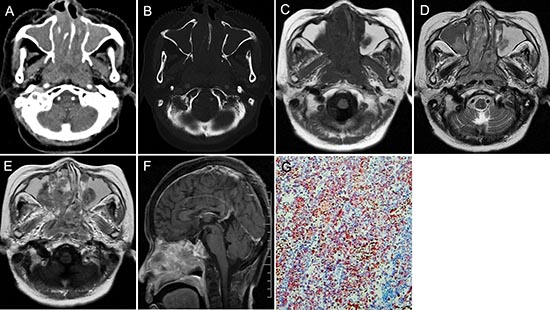

Figure 1: pPNET in a 63-year-old man. CT imaging showed an irregular nasopharynx mass with ill-defined borders. The mass had uneven enhancement (A). The sphenoid pterygoid demonstrated bone resorption (B). Precontrast MRI showed a hypo-intense mass on T1WI (C) and hyper-intense mass on T2WI (D). Enhanced MRI showed significant and heterogeneous enhancement (E). Sagittal enhanced MRI (F) images showed the mass invaded the slopes and anterior cranial fossa. The small round tumor cells were positive for CD-99 (G × 100).